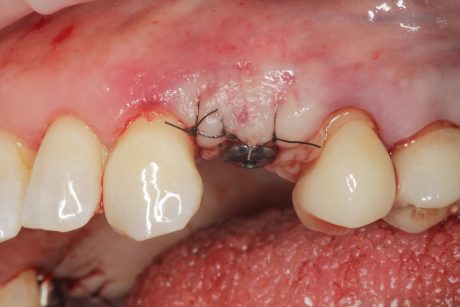

Il 20% degli impianti è stato posizionato nella mandibola (per lo più in posizione 47) e il restante 80% nel mascellare superiore (il 20% in posizione 16 e il 20% in posizione 25). Gli impianti posizionati nel mascellare superiore hanno trovato un osso tipo IV, mentre gli impianti posizionati nella mandibola hanno trovato un osso tipo III. Gli impianti utilizzati hanno un diametro compreso tra 4.0 e 4,5 mm (il 66.7% sono da 4.0 mm) e una lunghezza compresa tra 4.5 mm e 7.5 mm (il 53.3% sono lunghi 7.5 mm). Nell’86.7% dei casi non è stato eseguito alcun procedimento chirurgico aggiuntivo; in un caso, due impianti hanno previsto in rialzo di seno transcrestale con PRGF-Endoret e osso autologo. Nel 93.3% dei casi la protesizzazione ha previsto ponti avvitati a più elementi; un impianto è stato protesizzato mediante elemento singolo avvitato con componente transepiteliale. Il follow-up medio è stato di 12.4 ± 1.05 mesi dal carico. Il 100% degli impianti è sopravvissuto, senza complicanze né chirurgiche né protesiche. La perdita di osso media a 12 mesi è stata mesialmente di 0.15 ± 0.74 mm e distalmente di 0.13 ± 0.85 mm. La Figura 4 mostra l’osso perso su un singolo impianto e le Figure 5-14 illustrano un caso clinico rappresentativo.

Nella serie di casi clinici che abbiamo presentato, la combinazione di impianti Core-X® con il protocollo di chirurgia guidata Stop & Guide® è clinicamente efficace nel trattamento di casi caratterizzati da osso a bassa densità, anatomia compromessa o spazio interprossimale limitato.

La macro geometria implantare consente una densificazione ossea controllata e un’alta stabilità primaria senza manovre chirurgiche invasive.

Il sistema driver guidato consente un posizionamento implantare protesicamente guidato e preciso, minimizzando l’errore umano e preservando l’osso marginale.